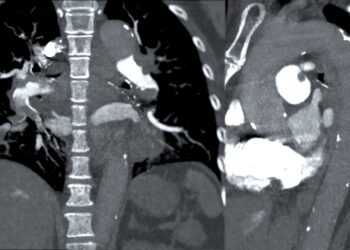

Kairysis skilvelis – tai viena iš keturių širdies kamerų. Jis užima apatinę kairę širdies dalį ir yra žemiau kairiojo prieširdžio,...

Dešinysis skilvelis yra viena iš keturių pagrindinių širdies ertmių, atliekanti svarbų vaidmenį kraujotakos procese – būtent ji varo deguonies stokojantį...